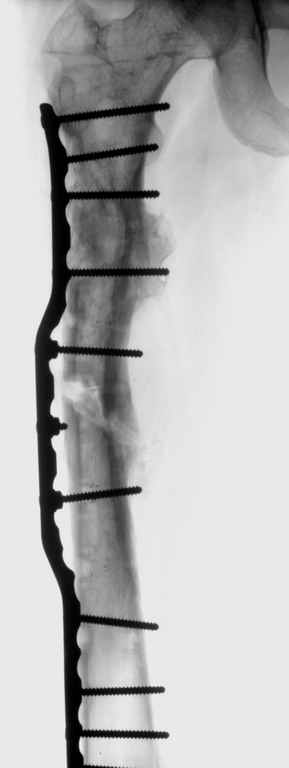

Leonid Pollyak 02 Январь 2005, 22:42

Хотелось бы показать, что получилось в результате.

Операция выполнялась с помощью А.Н.Челнокова. Очень понравилась технология выполнения блокируемого остеосинтеза с использованием спицевого дистрактора, модифицированный гвоздь с латерализованным проксимальным отделом и возможностью многовинтовой фиксации проксимального и дистального участков бедра.